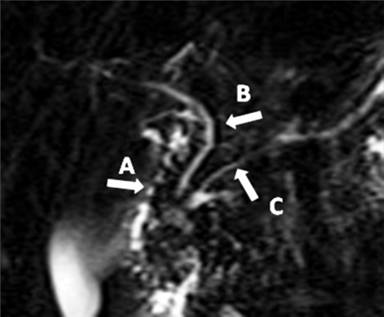

The currently 13-year-old Caucasian boy was first examined at our department at the age of 11 on account of acute abdominal pain, intense nausea and vomiting. His prior history included several similar episodes (approximately 2 attacks per year), some managed at home and others with brief hospitalization. The first episode occurred at the age of 2.5 with same symptoms and elevated serum amylase and lipase levels. Over the next years further investigations have been performed to determine the root cause of patient’s complaints and abdominal trauma, cystic fibrosis, infectious, metabolic, autoimmune, drug and systemic causes were gradually excluded, by means of anamnestic investigations, clinical observations and by laboratory evaluations. Attempting to exclude any structural anomaly, magnetic resonance cholangiopancreatography (MRCP) (Figure 1) and endoscopic retrograde cholangiopancreatography (ERCP) were performed and the diagnosis of chronic pancreatitis probably on the basis of pancreas divisum was established. Note that this finding was also excluded later (see below).

Figure 1. Magnetic resonance cholangiopancreatography (MRCP) image of the patient. By MRCP scan the diagnosis of chronic pancreatitis probably on the basis of pancreas divisum was suspected, but it was ruled out later by endoscopic retrograde cholangiopancreatography. A: duodenum; B: common bile duct; C: pancreatic duct |